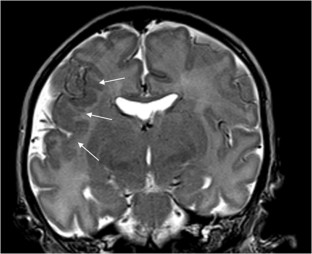

We selected pediatric head MRI examinations from 2005 to 2017 based on the finding of a double midline sellar and suprasellar bright spot on T1-weighted sequence. Medical history, physical examination, pituitary hormonal profile and bone age evaluation were extracted from the medical record of the selected patients. An experienced pediatric neuroradiologist reviewed head MRIs, which were performed on 3-tesla (T) magnet and included at least sagittal T1-weighted imaging centered on the sella turcica obtained with and without fat suppression.

In six cases, two midline bright spots were identified on T1-weighted sequences obtained both with and without fat suppression. While one spot was located at the expected site of the neurohypophysis in the posterior sella, the second one was in the region of the median eminence, suggesting partial ectopic posterior pituitary gland. Growth hormone deficiency, either isolated (n=1) or combined with thyroid stimulating hormone deficiency (n=1) was found. None of the children had clinical signs of posterior pituitary dysfunction.